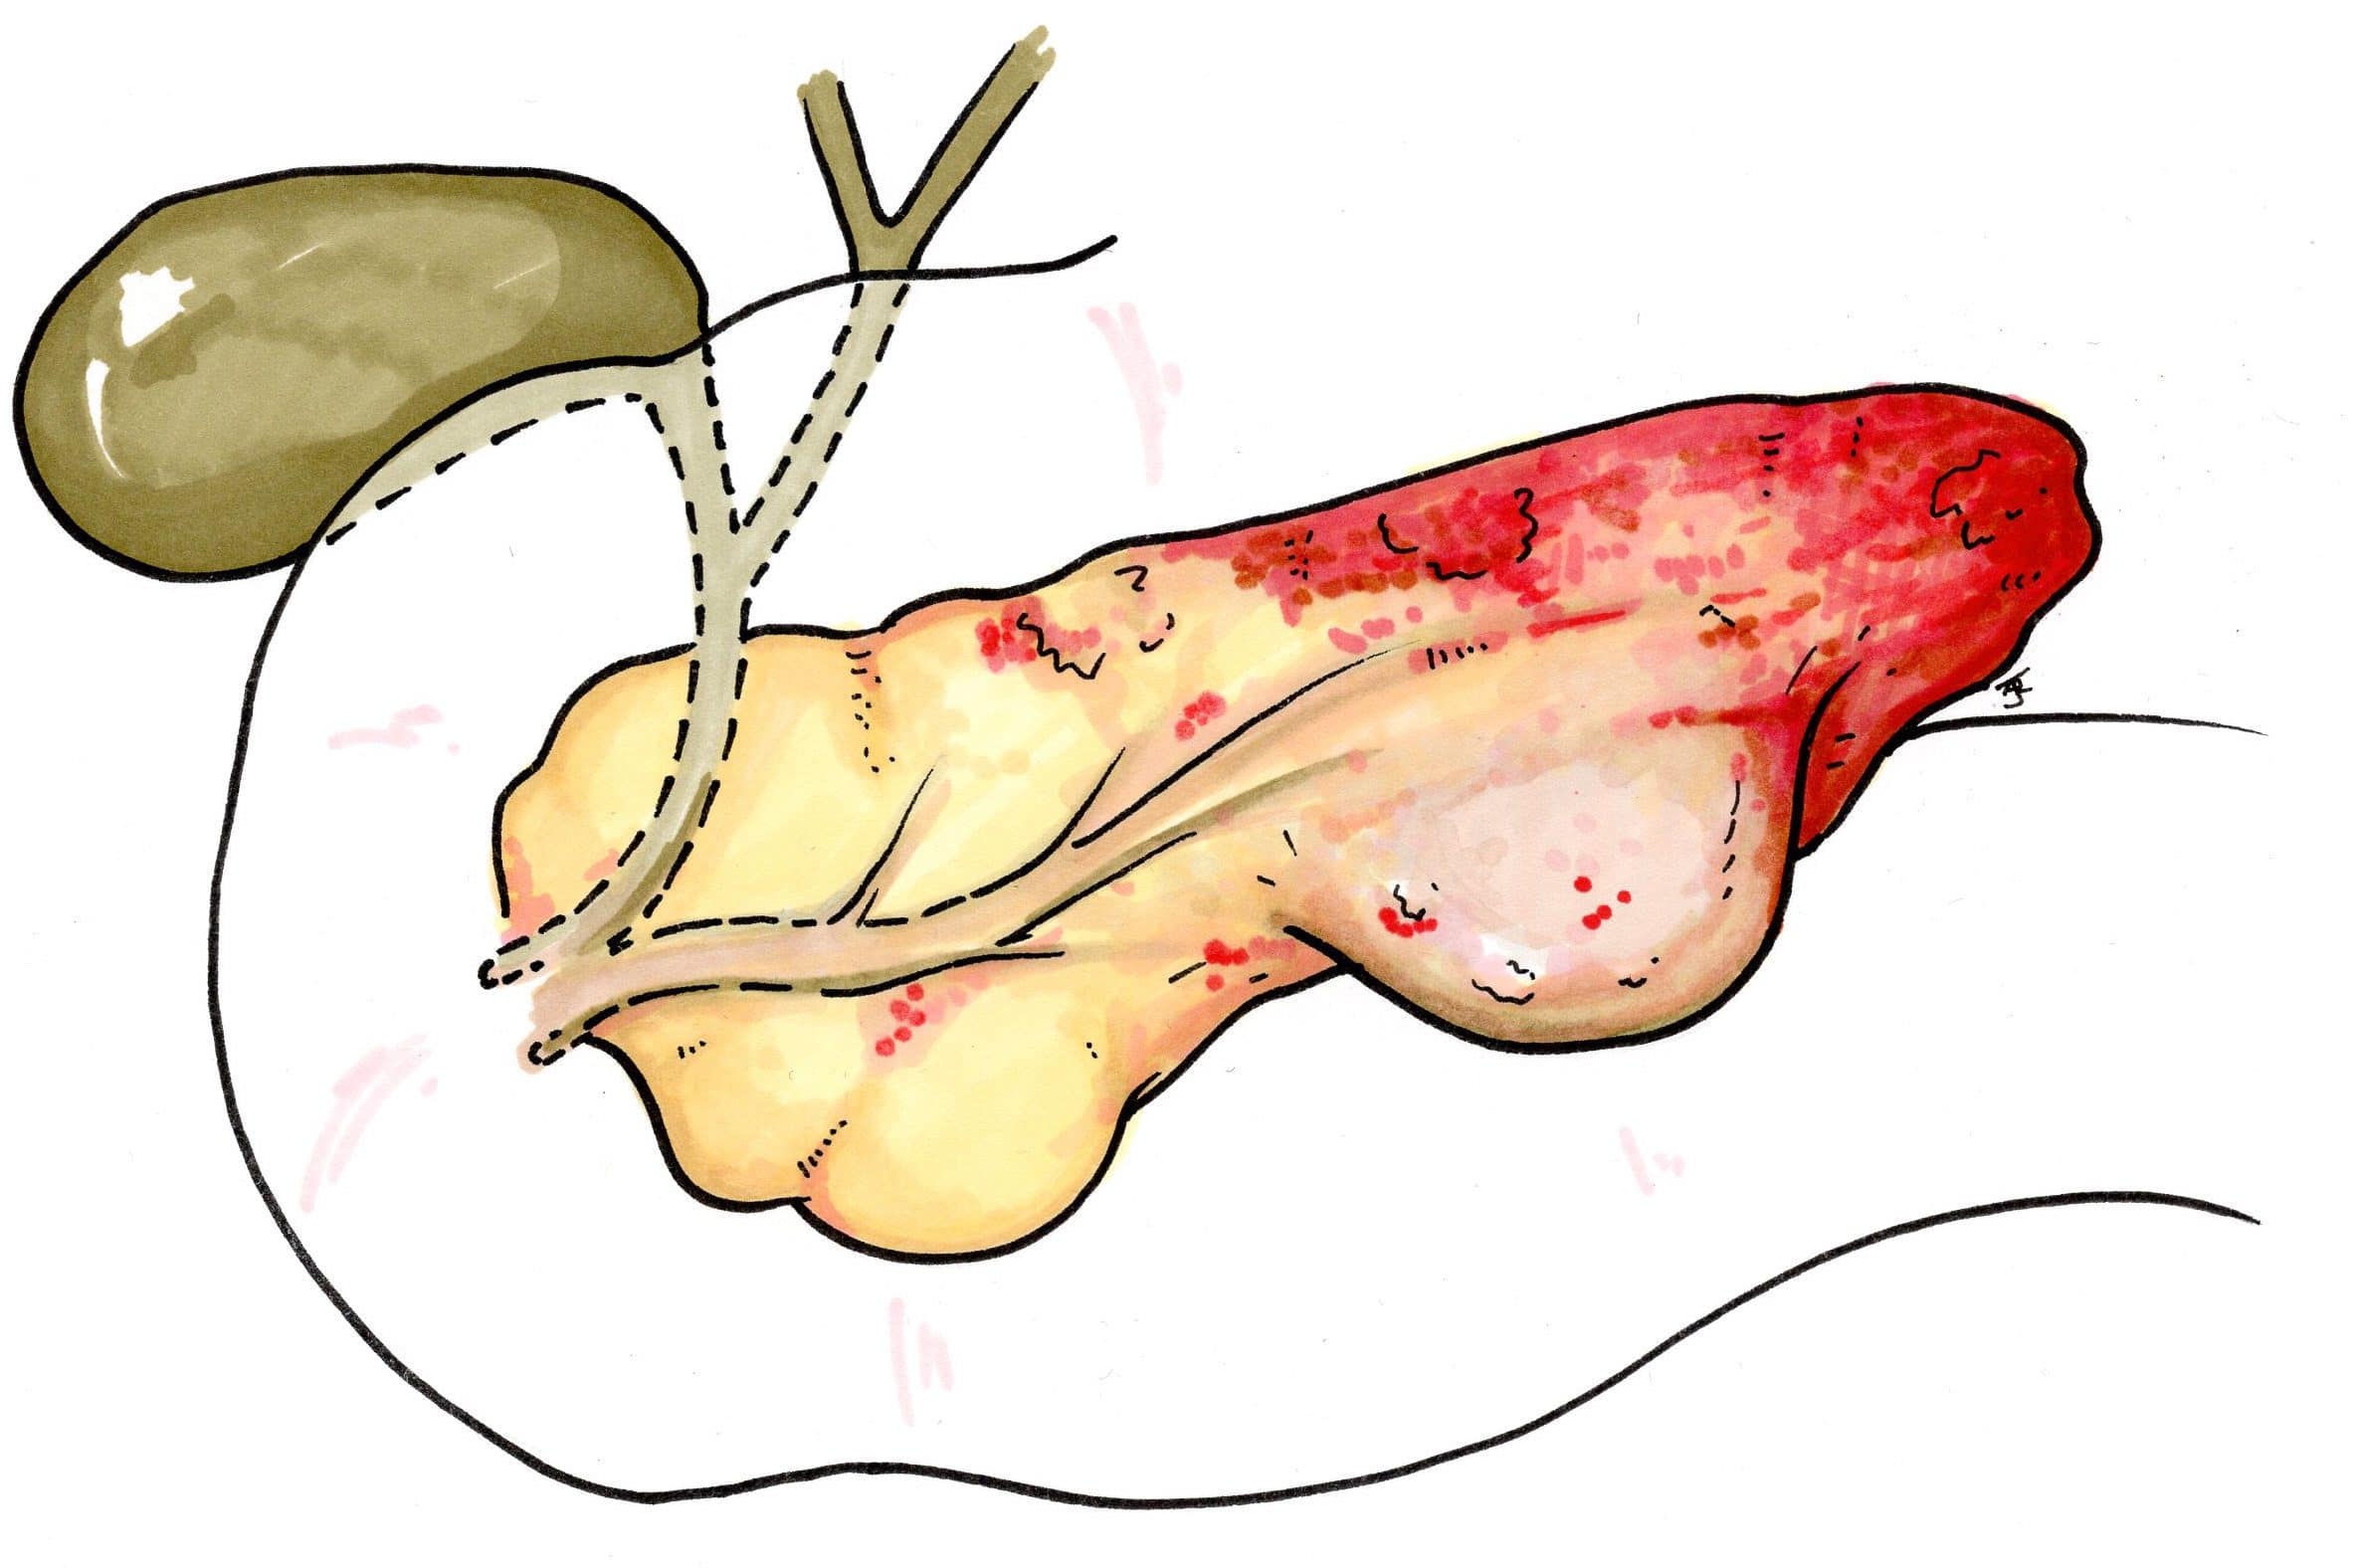

Pancreatic Necrosis

Ongoing inflammation eventually leads to ischaemic infarction of the pancreatic tissue, hence such progression should be suspected in patients with evidence of persistent systemic inflammation for more than 7-10 days after the onset of pancreatitis.

Any suspected pancreatic necrosis should be confirmed by CT imaging and treatment will often warrant pancreatic necrosectomy (open or endoscopic)*.

Pancreatic necrosis is prone to infection and should be suspected if there is a clinical deterioration in the patient associated with raised infection markers (or from positive blood culture or changes of low density within the pancreas on CT). Definitive diagnosis of infected pancreatic necrosis can be confirmed by a fine needle aspiration of the necrosis.

*General consensus for intervention in cases of confirmed pancreatic necrosis is to be delayed until walled-off necrosis has developed, typically 3-5 weeks after the onset of symptoms

Figure 5 – Schematic demonstrating a pancreatic necrosis